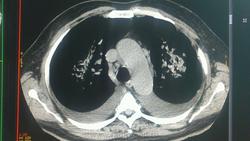

Мужчина 60 лет. Заболел остро около месяца назад с подъема температуры до 38, появился сухой кашель, слабость. Лечится в пульмонологии с диагнозом двусторонняя внебольничная пневмония. В анализах от 14.01 Hb147 , L7,9   СОЭ 22  от 16.01 Hb 144, L8,1   соэ 27   от 20.01 Hb 138 L9,0 соэ40

УЗИ плевральных полостей двусторонний гидроторакс.

В средостении единичные увеличенные до 14 мм. в поперечнике лимфоузлы паратрахеальной группы, некоторые с признаками инволюции. Дайкомы загрузить не получится, на работе интернет никакой, грузится до послезавтра будет.

Если по длиннику до 18,5 мм. увеличены паратрахеальные справа. Лимфоузлы с признаками инволюции- это я имела ввиду жировую перестройку.

Правые верхние паратрахеальные.

имхо: с учётом всей имющейся информации, предварительно предложил бы дифференциально-диагностический ряд:

1.Двухсторонняя полисегментраная плевропневмония, возможно вирусной этиологии.

2. Пневмония при острой ревматической атаке, поражения  с 2-х сторон относительно симмеричны, и напоминают " ревматическую бабочку".

3. С учётом поражения лимфатичских узлов паратрахеальной группы и острого начала не исключал бы версию лимфомы Ходжкина (лимфогранулематоза).

К сожалению да, т.к. отсутствует эффект от месячного лечения. По сравнению с предоставленными мне  Р-граммами динамики нет совершенно. МСКТ-исследование выполнено 23.01.14.